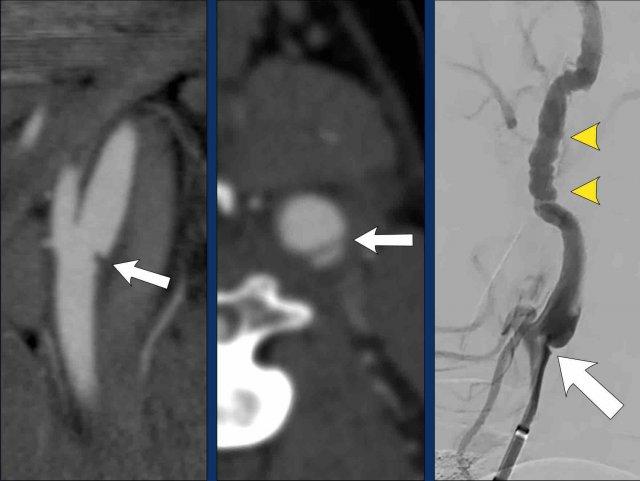

Bóc tách trên DSA

Tất cả các dấu hiệu đã thảo luận trên CTA đều tương tự và thậm chí rõ ràng hơn trên DSA.

- Catheter được đặt tại mức phình cảnh (bulbus), có hình ảnh bình thường.

Vài centimet phía trên phình cảnh, lòng mạch ICA bị lệch tâm và bị chèn ép bởi khối máu tụ thành mạch (thấy rõ hơn trên hình chi tiết số 2).

Tại mức nền sọ (đường chấm vàng), mạch máu trở về bình thường. - Hình chi tiết cho thấy thuốc cản quang đã thâm nhập vào trong khối máu tụ.

Lưu ý tổng đường kính ICA bị giãn rộng. Mũi tên chỉ lòng mạch thật sự. - Sau điều trị nội mạch, sự thông thoáng của ICA đã được phục hồi.

Khối máu tụ thành mạch phần lớn đã được tiêu huyết khối thông qua điều trị tĩnh mạch bằng chất hoạt hóa plasminogen mô tái tổ hợp (rt-PA, alteplase) trước khi can thiệp nội mạch. Vạt nội mạc (intima flap) vẫn còn nhìn thấy. Một lần nữa, bạn có thể thấy vạt nội mạc dừng lại tại mức nền sọ.